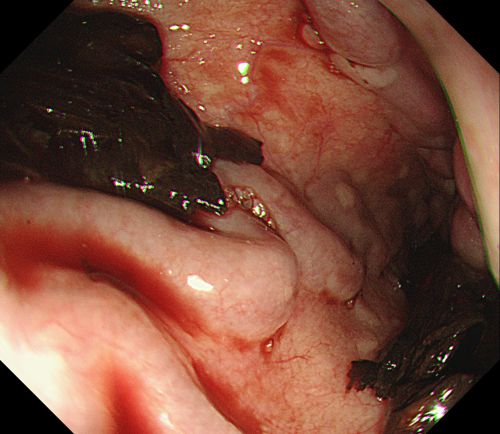

内镜下胃底可见大量血液及血凝块。

内镜下进行食管静脉曲张硬化剂注射治疗。

患者旋即被推入手术室,麻醉三科刘际童主任为其进行气管插管、全麻,保持呼吸道通畅,并进行中心静脉置管等维持血压平稳。综合内科彭娅主任进行胃镜治疗,发现患者重度食管静脉曲张,胃底可见大量血液及血凝块;小心翼翼抽吸血液及清洗血块后,寻找到“犯罪血管”,在内镜下进行食管静脉曲张套扎+硬化剂注射治疗,封闭出血血管。